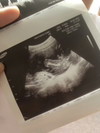

ท้องแรก ลูกชาย นอนชิวมาเลยค่ะ